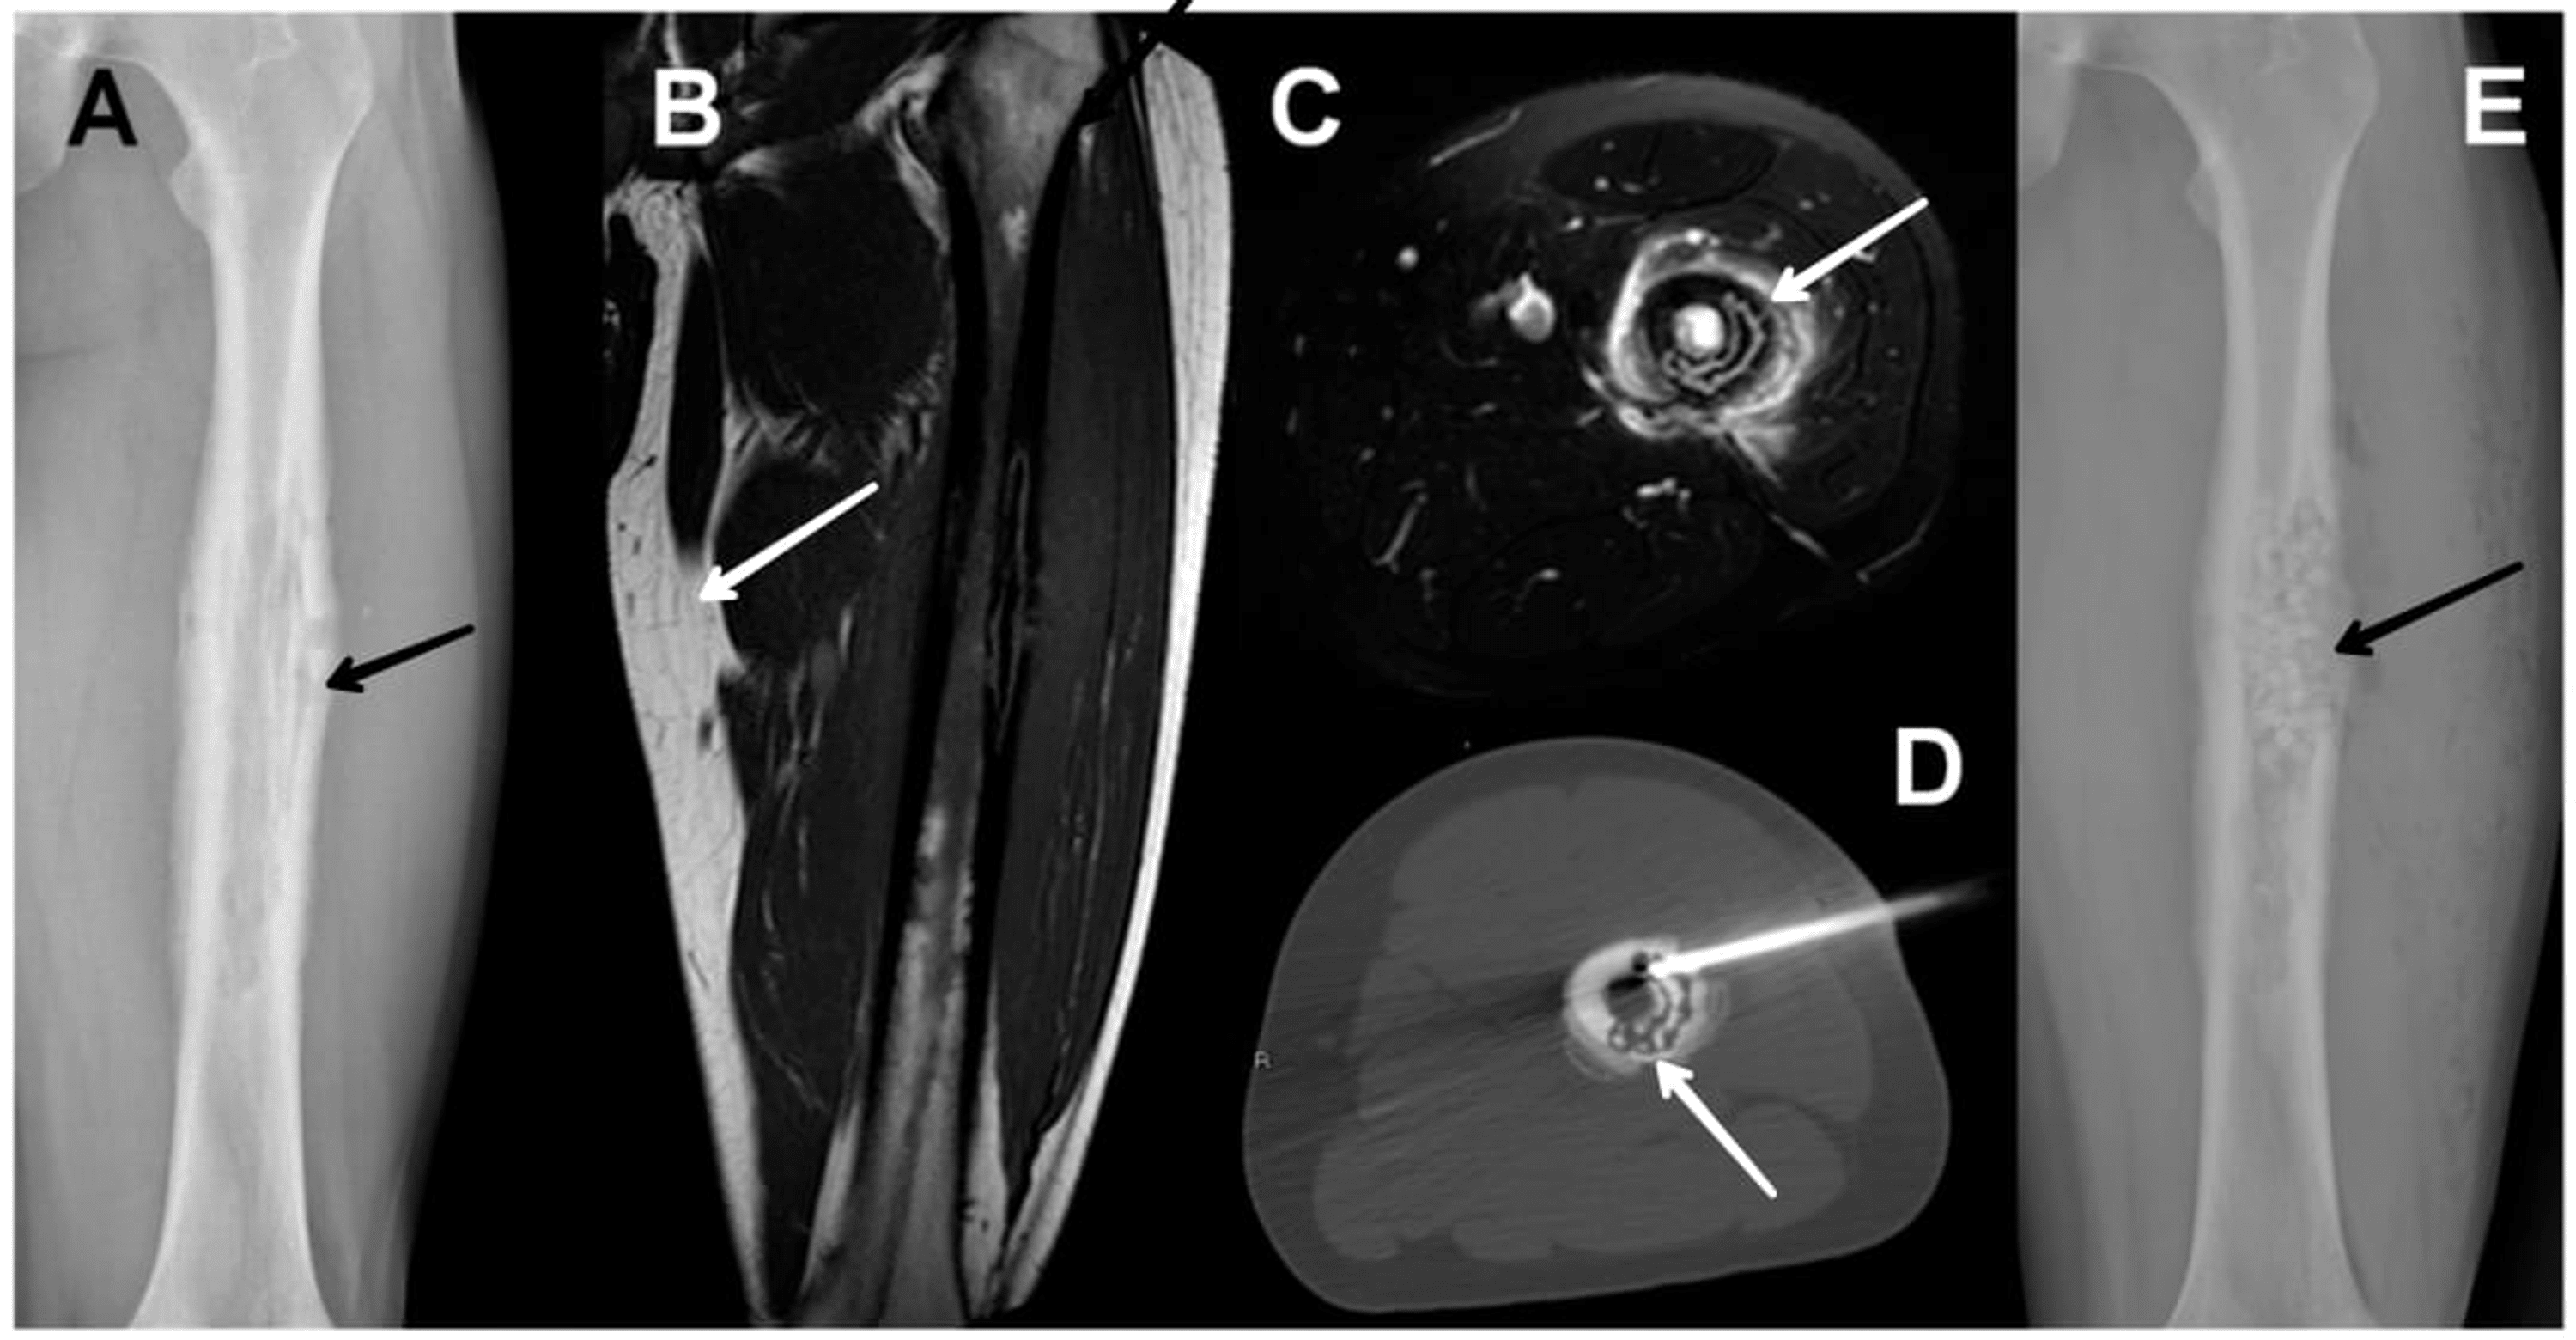

Figure 1 from Antibiotic Treatment of Vertebral Osteomyelitis caused by MethicillinSusceptible Staph Aureus Osteomyelitis Oral Treatment direct sampling of the wound for culture and antimicrobial sensitivity is essential to target treatment. — antibiotic regimens for the empiric treatment of acute osteomyelitis, particularly in children, should include an agent directed against s. — clindamycin has been successfully used against staphylococcal bone and joint infections, especially in. — a radiograph shows cortical erosions, and. Staph Aureus Osteomyelitis Oral Treatment.